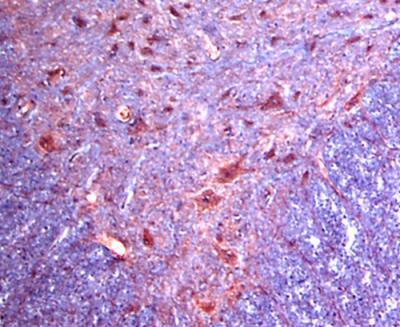

Supportive validation

- Submitted by

- Novus Biologicals (provider)

- Main image

- Experimental details

- Immunohistochemistry: alpha-2C Adrenergic R/ADRA2C Antibody [NB100-93554] - Staining of Alpha 2c Adrenergic Receptor in rat's ventral spinal cord. NB100-93554 was employed at a dilution of 1:100-1:300 and detection was carried out using HRP-AEC staining reagents (red color) followed by counterstaining with hematoxylin.